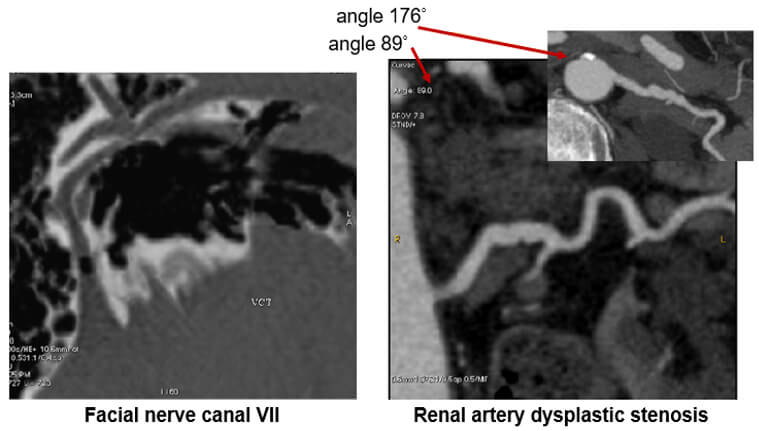

Post Processing

The curved post-processing algorithm allows for:

- Better visualization of a tract

- Better localization of a pathological element

- Better distance measurement (example: stenosis)

- This study can be done automatically through vascular HU or manually point by point

Images

The image on the left shows us the facial nerve while the image on the right shows renal artery dysplastic stenosis.